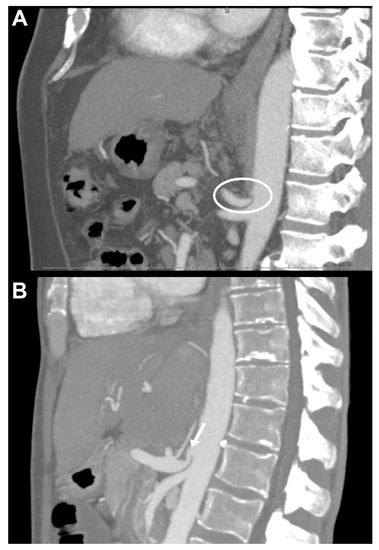

Figure 1. Preoperative computer tomography images of liver transplant recipients with median arcuate ligament compression (MALC) in the sagittal plane using maximal intensity projection. (A) Patient with severe median arcuate ligament (MAL) related occlusion. Note the hypertrophic MAL and the lack of continuous contrast in the celiac axis (circle). No calcified plaques were observed. Arterial revascularization was performed using an aorto-hepatic jump graft. (B) Patient with MALC. Note the hooked-like appearance of the celiac axis and the post-stenotic dilatation (arrow). MALC was released intraoperatively and standard branch-patch reconstruction could be performed with good outcome and without arterial complications.

All patients underwent preoperative contrast-enhanced computer tomography (ceCT). Three-dimensional reconstructions were generated with a maximal intensity projection [7]. In our clinical routine all CT scans are examined and demonstrated by a senior staff radiologist during our multidisciplinary liver transplantation board meetings and also by the consultant transplant surgeon immediately before transplantation, to assess vascular abnormalities as well as to plan the reconstruction approach and evaluate the potential need of surgical division of the MAL vs. alternative reconstruction during surgery. Within our study, however, all ceCT examinations were reassessed independently by two experienced staff radiologists (P.I., M.L.) who were blinded for the subsequent surgical treatment approach and postoperative outcomes. Extrinsic stenosis was due to MALC, defined as a characteristic (more than 50% in diameter) superior indentation on the proximal celiac axis usually about 5 mm from its origin at the abdominal aorta with post-stenotic dilatation as described before (Figure 1) [7,9]. Intrinsic stenosis due to atherosclerosis was registered if a significant calcified concentric stenosis was present [7]. Other vascular aberrancies and anatomical variations were registered as well.